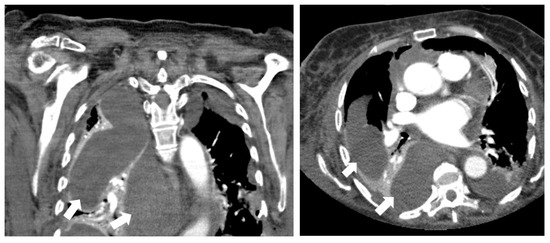

Figure 1. An 83-year-old woman with chambered pleural effusion (→) and CT attenuation of 8 HU. After percutaneous drainage, no pathogen was detected by microbiological approach.

Figure 2. A 63-year-old man with presacral abscess (*), demonstrating gas entrapment (→), wall enhancement (>), fat stranding and CT attenuation of 29 HU. Microbiology after percutaneous drainage confirmed infection.